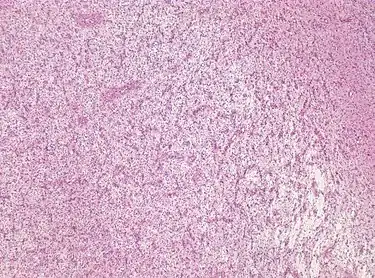

Photomicrograph displaying the AG tumor cells by histological evaluation, H&E stain. The striking characteristic of AG is that cells tend to cluster around brain blood vessels.[1]

Photomicrograph displaying the AG tumor cells by histological evaluation, H&E stain.Characteristics of AG: low Ki-67 proliferative rate, GFAP-positive, NeuN-positive, S-100-positive, Protein53-negative, Syn-negative, Olig-2-negative, CK-negative.[3]